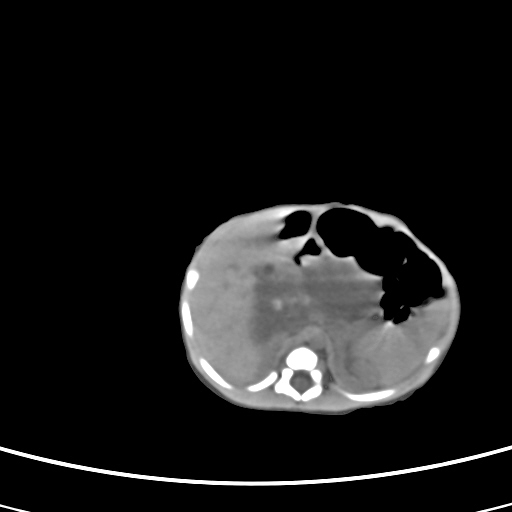

患儿,男性,出生后2天,在胎儿时b超已发现病变,患儿一般情况可。因病变部位偏向于右侧肾上腺区,目前考虑为神经母细胞瘤,不知各位能否支持。

反对定位在右肾上腺区的说法,那么神经母细胞瘤也可以暂时不予考虑。请看下图:

下面这幅图中,似乎可以见到肿瘤的薄包膜,其后与右肾之间的又是什么东西呢?这关系到肿瘤的定位、定性。我考虑病灶是位于肝十二指肠韧带内的畸胎瘤可能性比较大。请各位老师仔细看一下:

病灶巨大,位于右侧肾上腺区,与周围组织分界欠清,内见不规则钙化影,无明显脂肪组织,首先考虑神经母细胞瘤,但畸胎瘤不能排除。

支持守望可可西里分析。下腔静脉的位置很关键。

手术结果为畸胎瘤